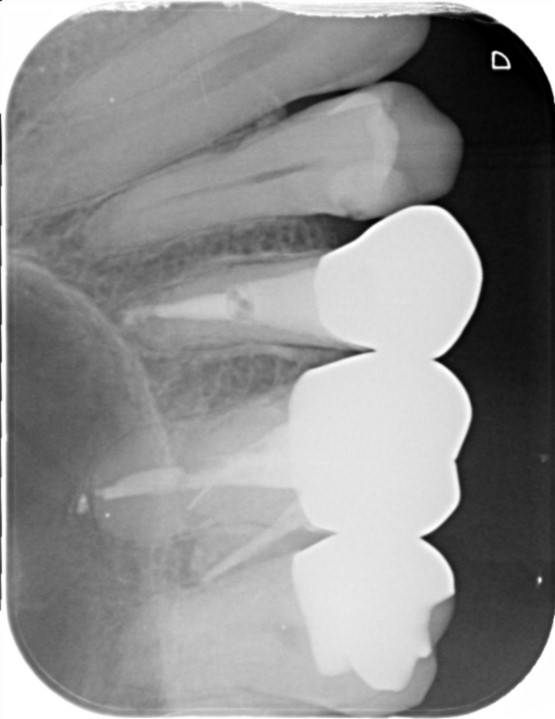

Case

40代女性

2023.8 左上6番破折の疑い

2024.12 左上6番抜歯

2025.7 インプラント埋入(以降インプラント治療継続中)

治療部位 左上6番

費用 約440000円

治療期間 7ヶ月

破折の疑い、腫れもあり義歯かインプラントのご提案をさせていただきました。

抜歯の時期も含めると約10ヶ月、治療方針を決めて進めていきました。